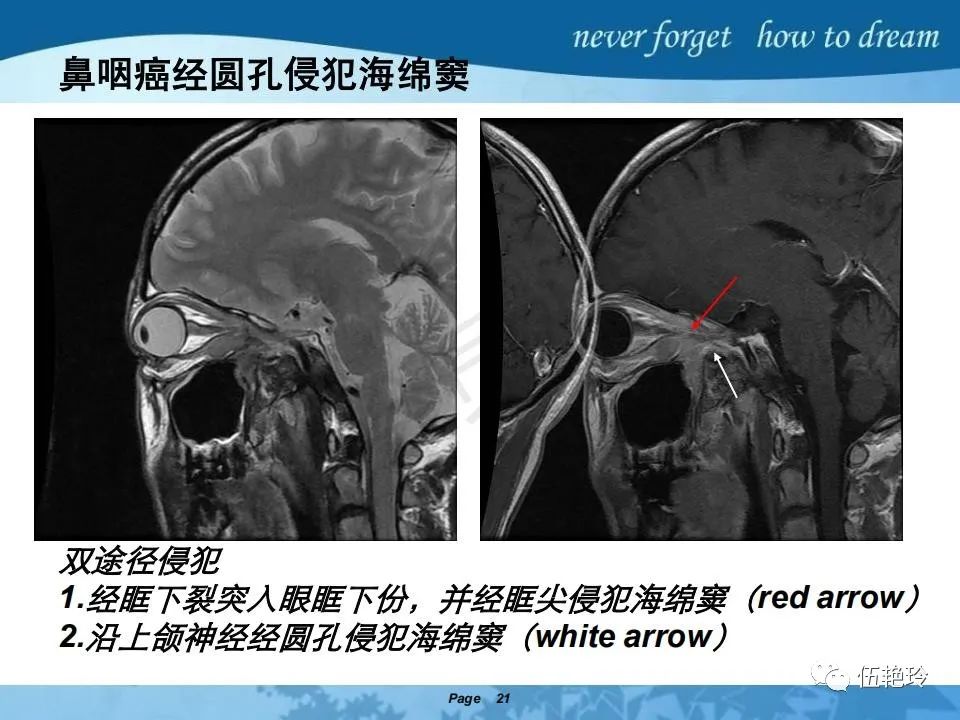

海绵窦区的解剖结构与鼻咽癌侵犯

2.2 鼻咽特有的解剖途径:鼻咽癌原发灶循序进展的总途径:鼻腔(47.8%)→翼腭窝(15.2%)→ 眶下裂(3.2%)→眶尖(1.2%)→海绵窦(0.6%)。

2.31 向上颅内:①鼻咽顶壁→破裂孔(岩尖、斜坡)→蝶窦、海绵窦;②鼻咽顶壁→蝶骨基底部→蝶窦、海绵窦;③鼻咽侧壁→茎突前间隙→蝶骨大翼(卵圆孔)→海绵窦;④鼻咽侧壁→茎突前间隙→翼腭窝→ 颞下窝;⑤鼻咽前壁→鼻腔→翼突、翼腭窝→眶下裂→眶尖→海绵窦;⑥鼻咽前壁→鼻腔→上颌窦、筛窦;